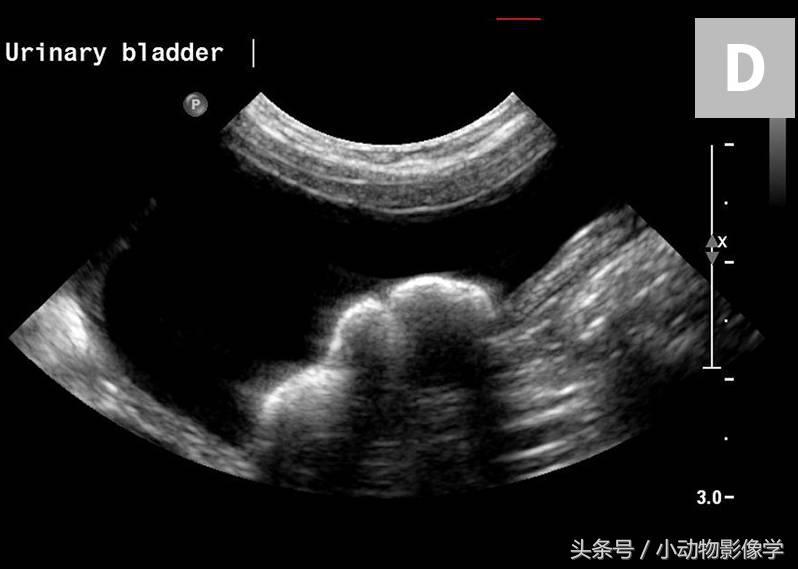

图8D、图8C中犬的超声图像。与图8B相比,此结石的边缘非常平滑。